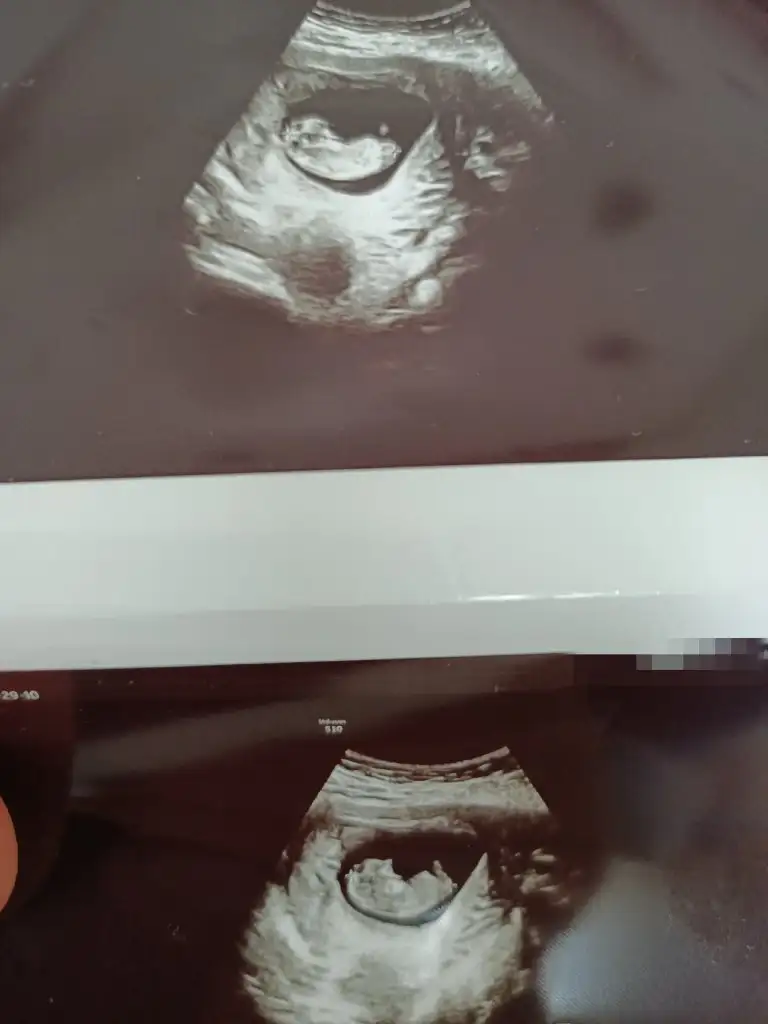

Canım bana da bakar mısın 6-8 ve 10. Haftalar

• IMG_20230329_153603.webp

IMG_20230329_153603.webp

17,1 KB · Görüntüleme: 48

• IMG_20230329_153533.webp

IMG_20230329_153533.webp

16,5 KB · Görüntüleme: 46

• IMG_20230329_153649.webp

IMG_20230329_153649.webp

16 KB · Görüntüleme: 51